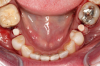

Fig 6. After splint removal (12 weeks postoperatively).

Figure 6

Fig 7. 12 weeks postoperatively.

Figure 7

Figure 3 through Figure 5 show the fitting of a one-piece multiple splint using a light-cured acrylic, along with flowable composite to adhere the splint to the three ceramic dental implants. The splint was to remain out of occlusion, without any occlusal forces for the 12-week osseointegration period. The patient was instructed to chew on the other side of her mouth for the 12 weeks before returning to the dental practice for simple removal of the splint. Removal of the splint revealed optimum results. The soft tissues were pink, with keratinized gingival margins completely surrounding the ceramic implants and consistent with what most dentists observe with the periodontium around periodontally healthy natural teeth (Figure 6 and Figure 7).